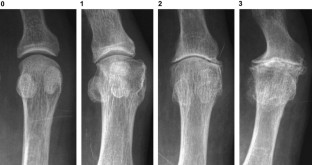

Fig. 1